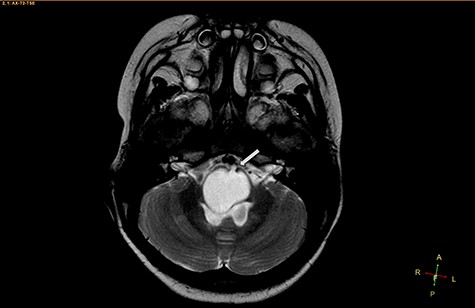

Axial T2-weighted image, showing a hyperintense, cystic mass inside the medulla oblongata. Exceptionally, the lesion appears to progress from extra-axial to intraparenchymal (arrow).

Two widely accepted hypotheses have been suggested to explain the establishment of extra-axial and intra-axial ECs. Theoretically, ECs form due to aberrations in ectodermal residues or the sequestration of ectodermal components during an early stage of gestational growth, between the 3rd and 5th weeks. The remnants of these ectodermal cells eventually proliferate, forming an EC [3, 4]. Retrospectively, the findings shown in Fig. 2 appear to show the progression of the lesions from the extra-axial to the intraparenchymal medulla oblongata; therefore, we have contributed additional evidence to reinforce the hypothesis regarding the primitively extra-axial root of EC development.